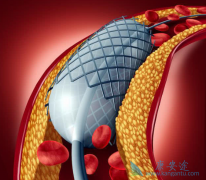

什么是 心脏支架手术 ?可以把心脏支架想象成是个细长的金属笼子,放在血管里就可以把即将堵死的血管撑开,心脏支架非常的细小,直径大约在2~4毫米,长几厘米,有空心、圆柱、网状金属管,一般都是用钛合金制成,是世界上最昂贵的一种金属。 心脏支 ...

不少人都听过心脏支架手术,这种手术堪称是当代心脏病学最伟大的一项发明。你知道这个小小的支架是怎么放到心脏里去的吗? 心脏支架 是通过介入手术的方式植入到人体的,我们可以从心脏介入手术可是说起,这样更好理解。心脏介入原理其实并不复杂。 ...

为了改善冠心病介入治疗短期和长期的疗效与安全性,所以研发了支架。第一代支架是金属裸支架,使冠心病介入治疗前进了一大步,使介入治疗变得非常安全,当血管发生严重狭窄时单纯球囊扩张预处理后,再用支架把血管完全撑开,就能解除心肌缺血危险,而且 ...

心脏支架 选哪种?放最好的支架?还是放最贵的支架?今天就给大家答疑解惑!心脏支架由具有强支撑力的合金制成,不同厂家支架的金属结构略有差别。心脏支架没有植入体内之前,包裹在球囊外面。植入时给球囊加压,支架打开至预定直径,使支架与血管壁完 ...